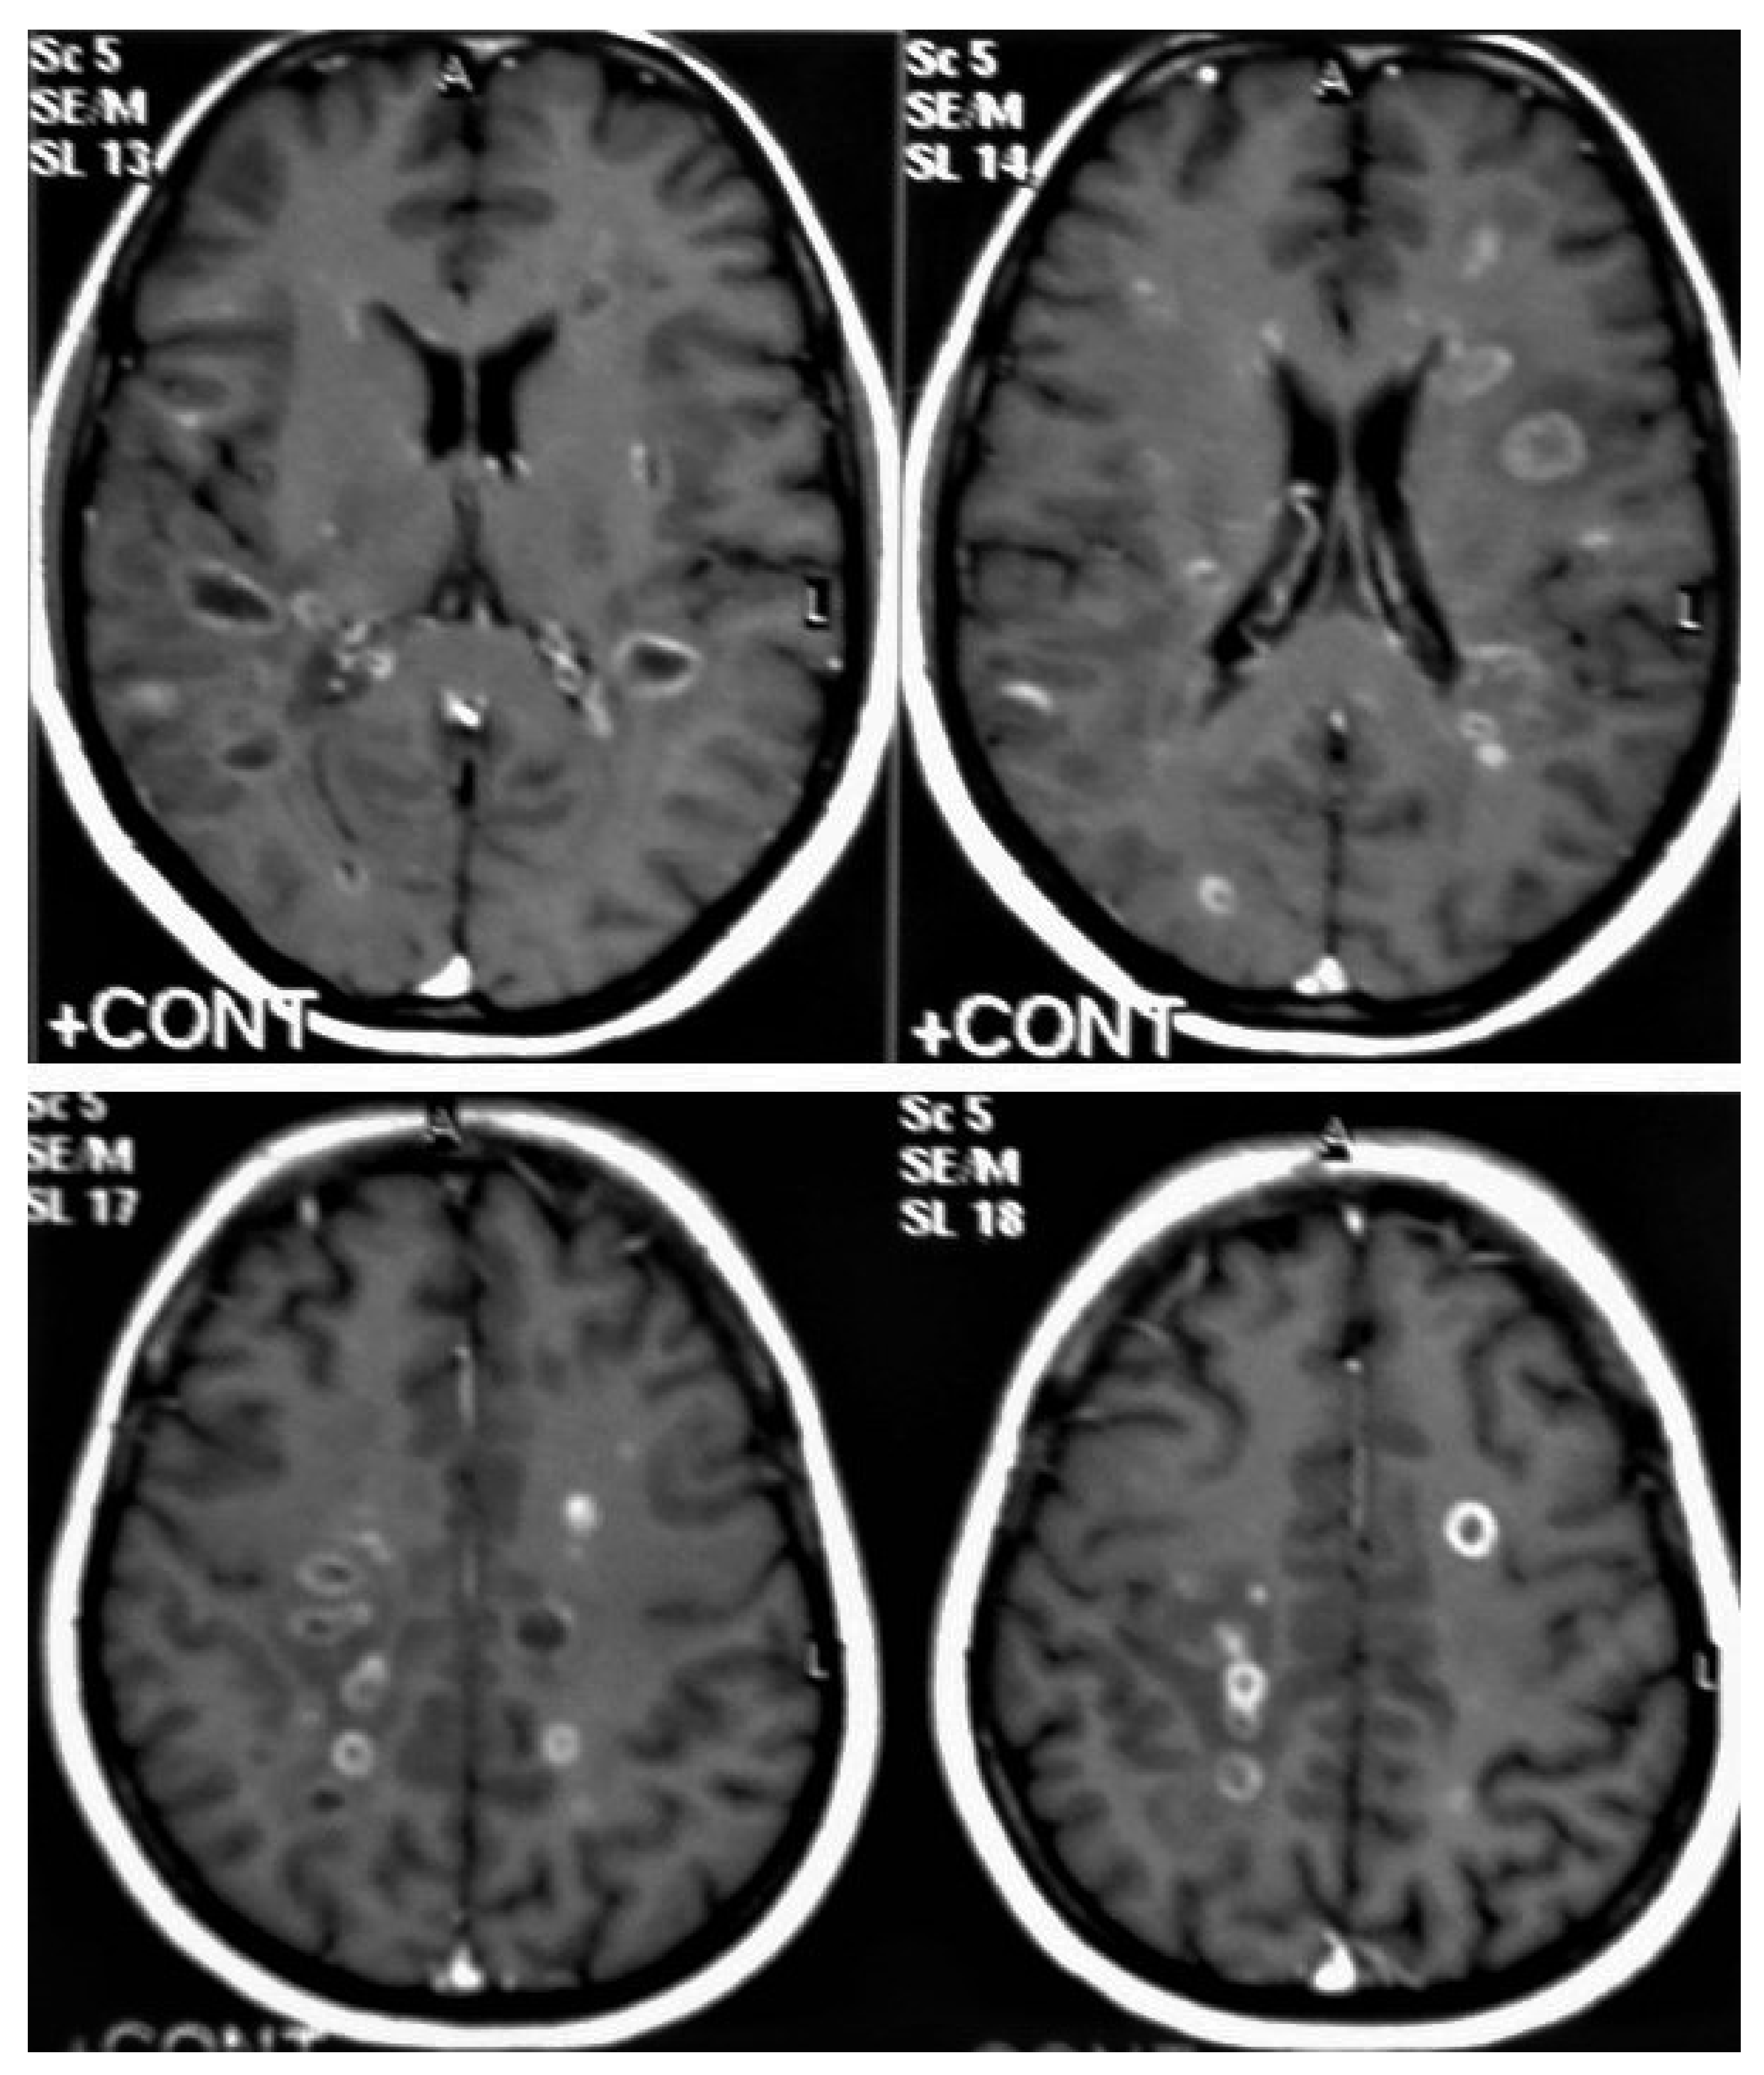

• Tuberculoma (Tuberculous granuloma; Figure 12 and Figure 13) is one of the most common brain parenchymal tuberculous lesions and can be solitary or multiple anywhere within the brain. It is commonly seen at the corticomedullary junction and periventricular region as a result of hematogenous dissemination. MRI features of tuberculoma vary according the stage of maturation (stage 1, non-caseating; stage-2, caseating granuloma; stage 3, caseating granuloma with central liquefaction; and stage 4, calcified granuloma). Radiologically, each stage of brain tuberculoma can mimic a wide variety of differential diagnoses, such as neurocysticercosis, fungal granulomas, pyogenic abscess, metastasis, glioma, lymphoma, and toxoplasmosis [25,27]. Ring-enhancing lesions of the brain may form a diagnostic dilemma [30].

• Miliary tuberculomas (Figure 13) occur due to the haematogenous dissemination of Mycobacterium tuberculosis bacilli, which are usually lung focused and occur especially in immunocompromised patients. They appear as innumerable small (2–3 mm) non-caseating granulomas with random distribution in the brain with a predominance to a gray-white matter junction as a result of hematogenous dissemination [25,26]. Miliary TB usually strongly mimics brain metastasis [31].

Figure 13. Multiple tuberculomas in an adult man. Selected MRI axial images post-contrast T1-weighted images show multiple small ring-enhancing lesions distributed in both cerebral hemispheres, with no significant surrounding cerebral edema, as is consistent with cerebral tuberculomas.